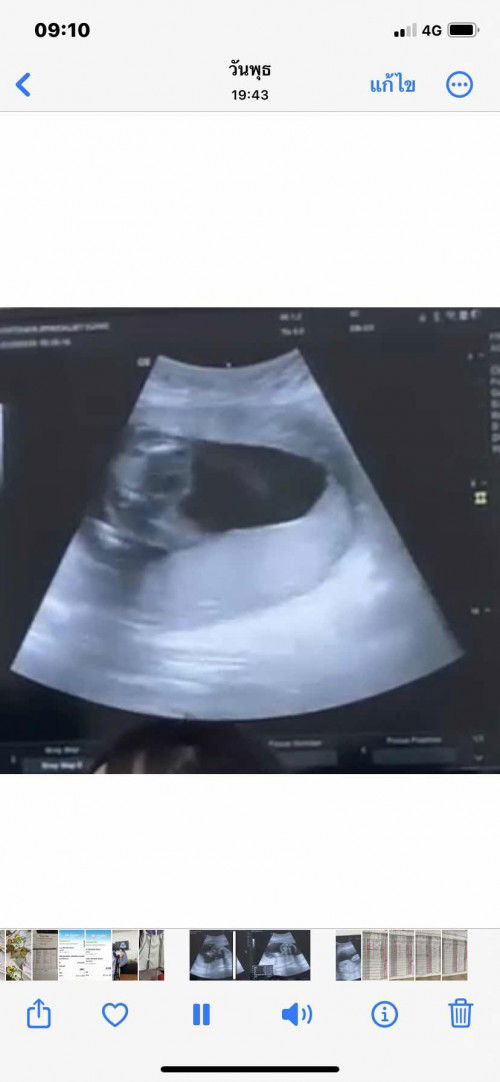

ไปหาหมอมาเมื่อวันที่ 1 ก.พ. เมื่อกี้ 21w3d หมอบอก ลูก นน. 553 กรัมแล้ว ลูกน้ำหนักดีนะแม่ หมอบอก แม่แอบตกใจ เพราะครั้งที่แล้ว นน.แค่ 100 กว่าๆเอง น้องเป็นผู้ชาย ดิ้นเก่งด้วย ตอนหมอซาวน์ก็ยังดิ้นๆอยู่ จริงๆแม่แอบกลัวลูกไม่แข็งแรงเพราะแม่ ทำงานหนักทุกวัน ทั้งยืนทั้งเดิน ทั้งวัน ตั้งแต่ 7 โมงเช้า ถึง 4 ทุ่ม ไม่ได้พักเลย